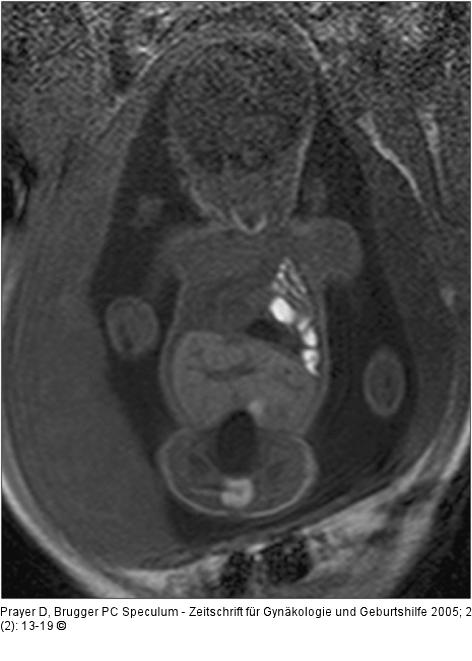

Abbildung 4: Pränatale Magnetresonanztomographie Fetus in der 32. SSW mit linksseitiger kongenitaler Zwerchfellhernie, koronale Schichtführung. Mit Hilfe der hier verwendeten Kontrastparameter können intrathorakal mit Mekonium gefüllten Darmanteile sehr hell dargestellt werden. Die Leber, sie ist etwas weniger hell als Mekonium, liegt intrabdominal. Am Hals ist auch die Glandula thyroidea zu erkennen. |

Fetus in der 32. SSW mit linksseitiger kongenitaler Zwerchfellhernie, koronale Schichtführung. Mit Hilfe der hier verwendeten Kontrastparameter können intrathorakal mit Mekonium gefüllten Darmanteile sehr hell dargestellt werden. Die Leber, sie ist etwas weniger hell als Mekonium, liegt intrabdominal. Am Hals ist auch die Glandula thyroidea zu erkennen. |